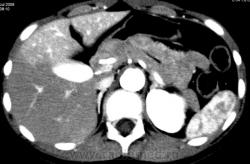

Nela. КТ аорты. Расслаивающаяся аневризма аорты.

Это расслоение произошло после баллонопластики коарктации аорты.

Расслоение продолжается ниже почечных артерий и заканчивается на левой общей подвздошной артерии. На уровне почечных артерий истинный просвет едва виден, местами теряется. Забрюшинно гематома.

Все возникло остро. Это девочка-подросток. Стент установить не удалось, слишком узкий истинный просвет. Пытались прооперировать, но через несколько часов после операции девочка умерла.